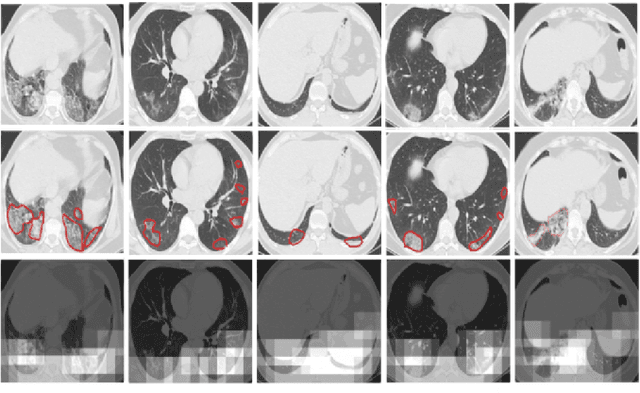

Abstract:The novel corona-virus disease (COVID-19) pandemic has caused a major outbreak in more than 200 countries around the world, leading to a severe impact on the health and life of many people globally. As of mid-July 2020, more than 12 million people were infected, and more than 570,000 death were reported. Computed Tomography (CT) images can be used as an alternative to the time-consuming RT-PCR test, to detect COVID-19. In this work we propose a segmentation framework to detect chest regions in CT images, which are infected by COVID-19. We use an architecture similar to U-Net model, and train it to detect ground glass regions, on pixel level. As the infected regions tend to form a connected component (rather than randomly distributed pixels), we add a suitable regularization term to the loss function, to promote connectivity of the segmentation map for COVID-19 pixels. 2D-anisotropic total-variation is used for this purpose, and therefore the proposed model is called "TV-UNet". Through experimental results on a relatively large-scale CT segmentation dataset of around 900 images, we show that adding this new regularization term leads to 2\% gain on overall segmentation performance compared to the U-Net model. Our experimental analysis, ranging from visual evaluation of the predicted segmentation results to quantitative assessment of segmentation performance (precision, recall, Dice score, and mIoU) demonstrated great ability to identify COVID-19 associated regions of the lungs, achieving a mIoU rate of over 99\%, and a Dice score of around 86\%.